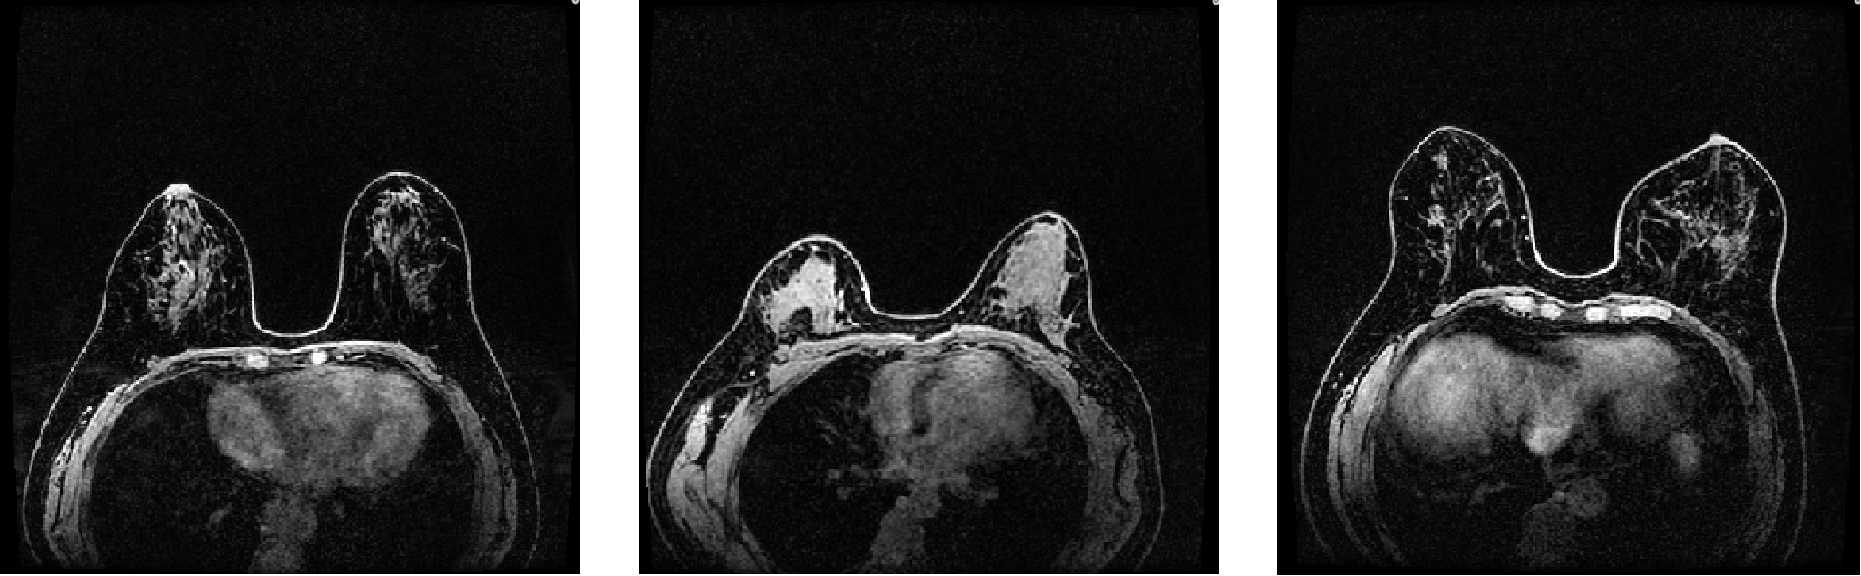

FGTSA toolkit is a Python package, which is able to detect/segment Fibroglandular Tissue regions and calculate relevant quantitative imaging biomarkers (e.g., background parenchymal enhancement, BPE) in breast MRI scans, which are highly associated with breast cancer risk, treatment response and prognosis.

FGTSA uses Fuzzy c-Means clustering (FCM) as a default method, which is a commonly used method for FGT segmentation. Note that, we are also developing other algorithms that will be released soon.

The enhancement of normal fibroglandular tissue observed at contrast-enhanced breast MRI is known as background parenchymal enhancement (BPE). The degree of BPE is typically assessed in four qualitative categories (minimal, mild, moderate, or marked) in clinical practice, which is required reporting during MRI interpretation in Breast Imaging Reporting and Data System (BI-RDS, fifth edition). FGTSA provides elaborate calculation for BPE report in percentage. The formular BPE expression is as follows: